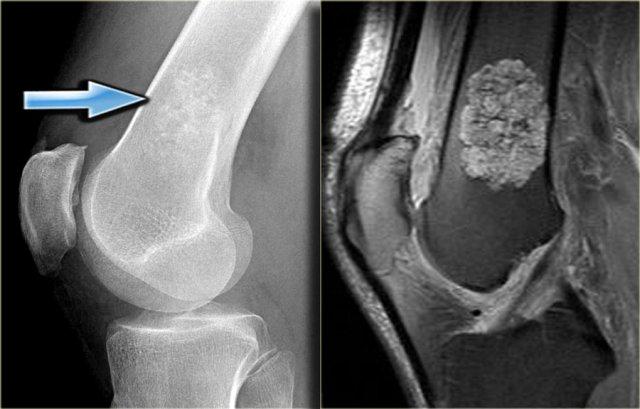

Đây là tổn thương nằm ở vùng đầu xương và hành xương của đầu trên xương cánh tay.

Tổn thương chủ yếu bị vôi hóa.

Hình ảnh T1W mặt phẳng vành tai cho thấy bờ tổn thương có dạng thùy và tín hiệu thấp ở ngoại vi do các vôi hóa.